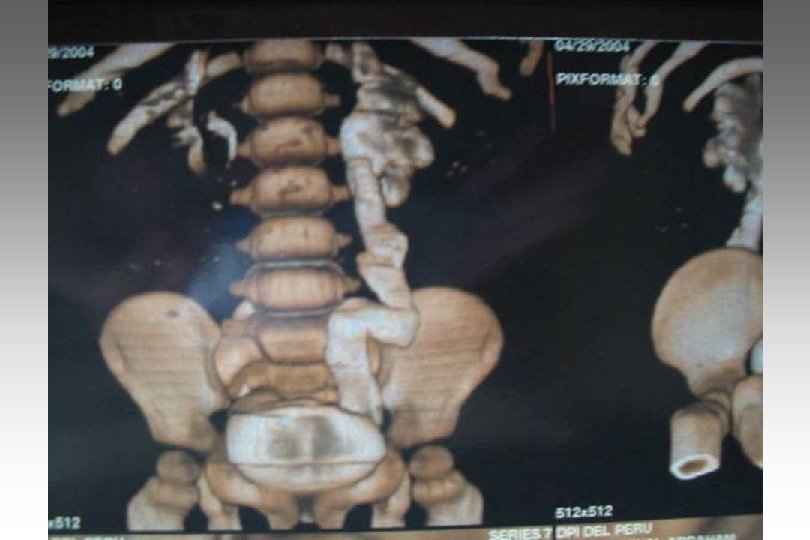

SECUENCIA DE IMAGEN o ECOGRAFIA. o CISTOURETROGRAFIA RETROGADA POST MICCIONAL. o PIELOGRAFIA ENDOVENOSA o GAMMAGRAFIA RENAL CON DMSA-TC 99. o RADIORENOGRAMA o UROGRAFIA POR RMN o TAC HELICOIDAL o ENDOSCOPIA VIRTUAL